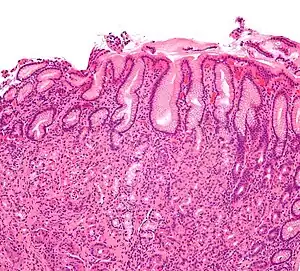

Micrograph showing gastritis. H&E stain.

Mucous gland metaplasia, the reversible replacement of differentiated cells, occurs in the setting of severe damage of the gastric glands, which then waste away (atrophic gastritis) and are progressively replaced by mucous glands. Gastric ulcers may develop; it is unclear if they are the causes or the consequences. Intestinal metaplasia typically begins in response to chronic mucosal injury in the antrum and may extend to the body. Gastric mucosa cells change to resemble intestinal mucosa and may even assume absorptive characteristics. Intestinal metaplasia is classified histologically as complete or incomplete. With complete metaplasia, gastric mucosa is completely transformed into small-bowel mucosa, both histologically and functionally, with the ability to absorb nutrients and secrete peptides. In incomplete metaplasia, the epithelium assumes a histologic appearance closer to that of the large intestine and frequently exhibits dysplasia.[18]